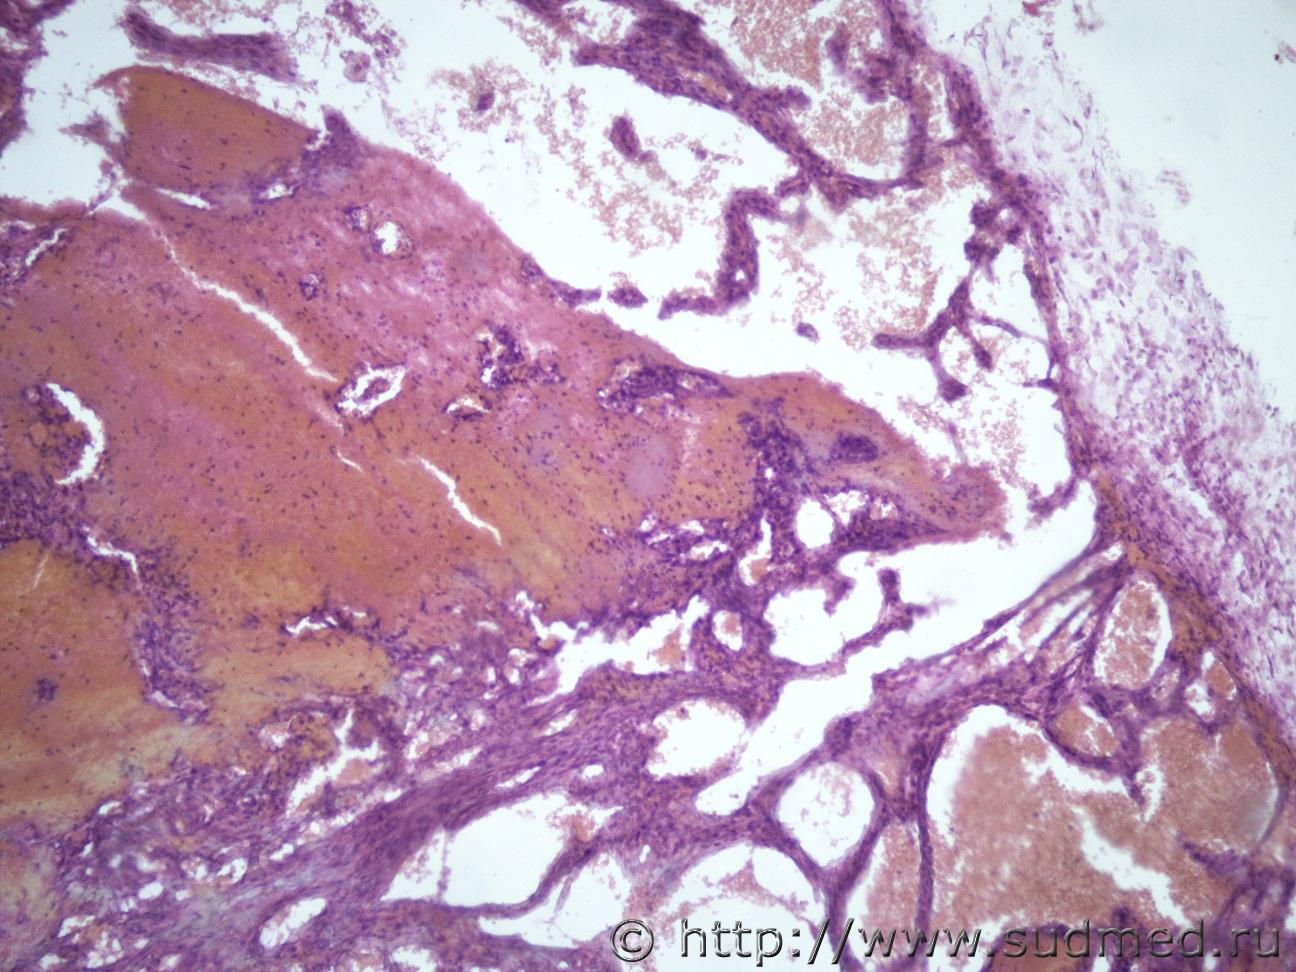

Ув. коллеги, может это тема не для нашего форума, но вдруг у кого нибудь будут идеи по этому поводу. В течении месяца выросло образование за ухом у лабораторной крысы округлой формы, плотно-эластической консистенции, в диаметре 1 см. Хозяин крысы подумал, что это абсцесс и решил сделать пункцию, после прокола истекло приличное количество крови и в течении 10-20 мин крыса скончалась. Макро- образование округлой формы, в тонкой капсуле, строма в виде ячеек, с кровоизлияниями.Судебная медицина - Прикрепленное изображение Судебная медицина - Прикрепленное изображениеСудебная медицина - Прикрепленное изображениеСудебная медицина - Прикрепленное изображениеСудебная медицина - Прикрепленное изображение

Похоже на кавернозную гемангиому .

Я тоже об этом подумала, но как она выросла за 1 мес, достаточно внушительных размеров для грызуна.

кавернозную гемангиому .

Аналогично.Зла здесь нет.